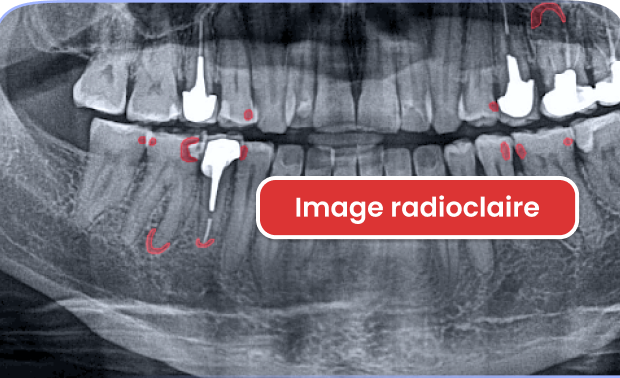

Aide au diagnostic

Avec Allisone, utilisez le dispositif médical Français d’aide au diagnostic et gagnez en sérénité & en confort de travail.

de détection de lésions périapicales

de détection de caries